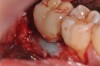

The surface of the implant had recombinant platelet-derived growth factor-BB applied after thorough rinsing of the citric acid and a composite graft of mineralized freeze-dried bone mixed with the PDGF-BB and enamel matrix derivative.

Figure 3